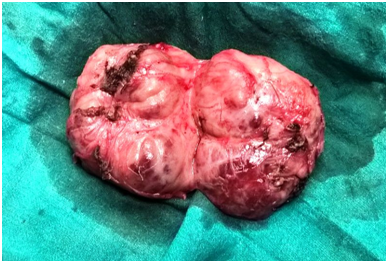

Paragangliomas can develop anywhere along the midline of the retroperitoneum. The exact incidence of retroperitoneal paragangliomas is unknown, although males are typically affected more frequently than Females. In addition, most patients are diagnosed between 30 and 45years of age.1 Clinically, patients with a retroperitoneal paraganglioma often present with back pain or a palpable mass.2 Conventional treatment for paragangliomas typically involves complete surgical excision, while surgical debulking is considered a mainstay of palliative therapy for malignant paragangliomas. In some cases, complete excision is difficult due to the highly vascular nature of paragangliomas and their proximity to major blood vessels (Figure 1-4).

Figure 2 Intraoperative photograph of tumor in-situ.

Figure 3 Excised tumor.